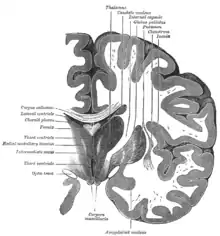

Корональний розтин мозку через третій шлуночок.

Горизонтальний розтин правої півкулі головного мозку.